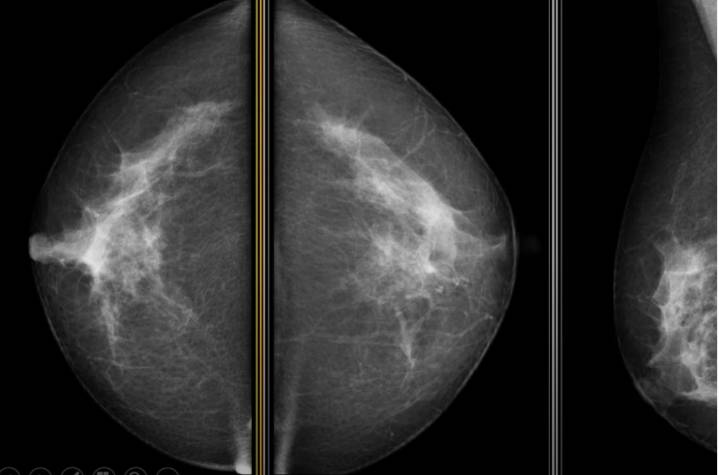

La Consejería de Sanidad del Gobierno de Aragón ha rechazado la solicitud del Ministerio de Sanidad para remitir los datos del programa de cribado de cáncer de mama en Aragón , alegando un incumplimiento técnico por parte del Ejecutivo central. El Gobierno aragonés considera que el Ministerio no ha habilitado la plataforma informática prometida, esencial para volcar la información de manera «homogénea y estructurada».

Esta negativa se suma a la postura de otras comunidades gobernadas por el PP, como Galicia, Valencia y Murcia, que también han objetado la petición de la ministra Mónica García, quien busca realizar una «valoración conjunta» de los programas de detección precoz de cáncer de mama , colon y cérvix.